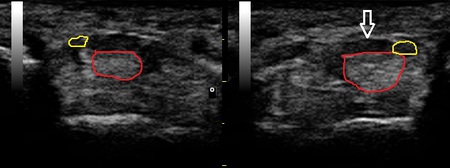

右手首 正常(健)側 左手首 超音波短軸像

川越市若葉 50代男性会社員、ベーシスト。 左手指の痛み、痺れ。 手根管狭窄症。

特に毎朝は手が浮腫んではばったく、指が曲がりづらいそうです。超音波検査を行ったところ、左の

指の屈筋腱が健側と比較して肥厚していました(画像の赤丸)。さらに左母指の屈筋腱も健側よりも

太くなっていました(画像の黄色丸)。

太くなった屈筋腱が手根管のスペースを狭くし画像矢印の正中神経を圧迫していることが痺れの

原因ではないかと考えられます。